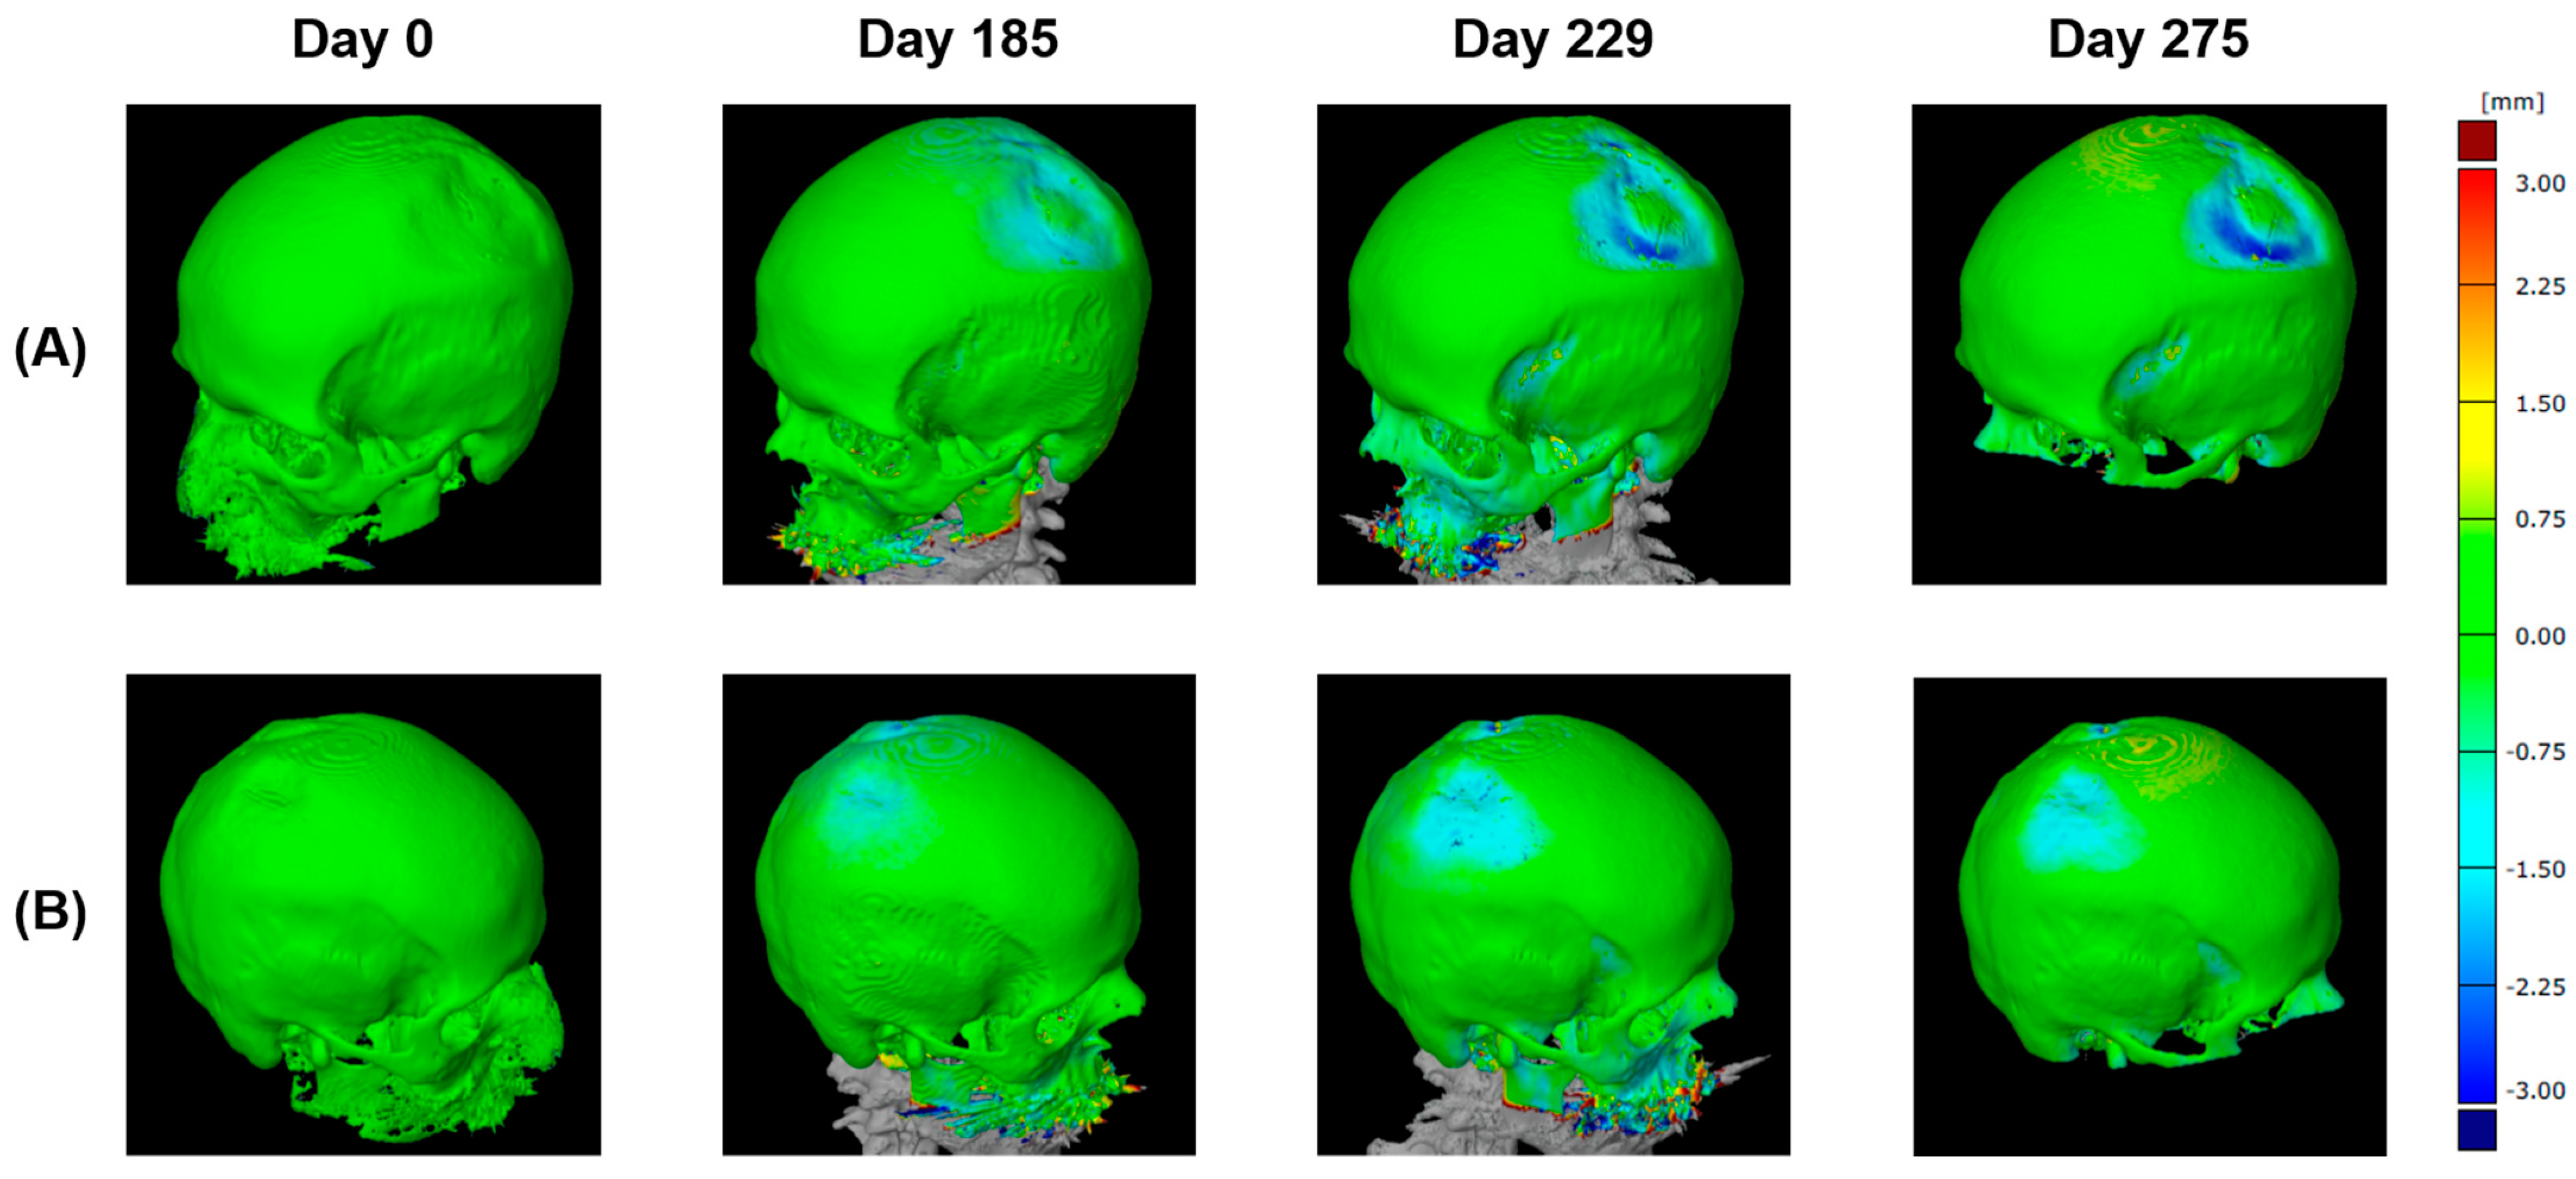

2.2.4. Three-Dimensional (3D) Measurement Method

3.4. Three-Dimensional (3D) Measurements of Biparietal Thinning

3.5. Comparisons of Changes in Bone Loss over Time